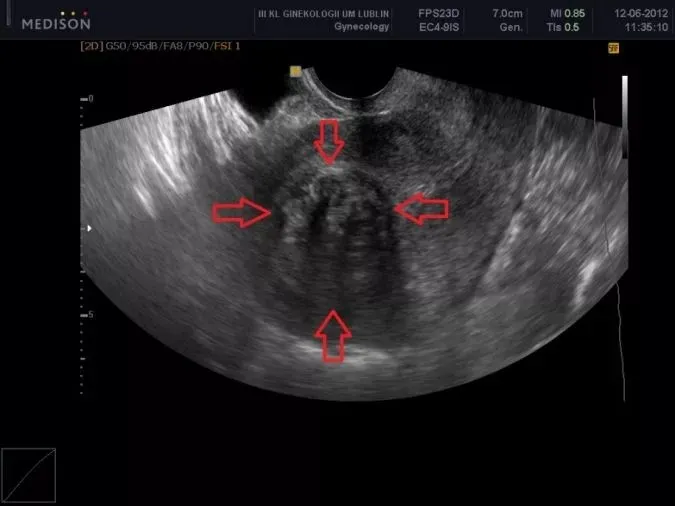

Rola regularnych badań USG w monitorowaniu stanu guzów

Podstawowym i niezastąpionym narzędziem diagnostycznym oraz monitorującym stan mięśniaków po menopauzie jest przezpochwowe badanie USG. Pozwala ono na ocenę wielkości, liczby i lokalizacji mięśniaków, a także na wykrycie ewentualnych zmian w ich strukturze. Regularne wykonywanie tego badania pozwala na wczesne wykrycie wszelkich niepokojących zmian, takich jak nagły wzrost guza.